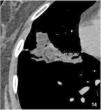

High-resolution computed tomography (HRCT) is the imaging method of choice for the evaluation and diagnosis of interstitial lung diseases because it confirms the presence of lung disease and establishes the correct diagnosis for associated complications. Nevertheless, the definitive diagnosis of these entities requires the imaging findings to be interpreted together with their clinical manifestations and histological confirmation. In this group of diseases, HRCT findings play a fundamental role, being especially important for avoiding unnecessary biopsies. For these reasons, clinicians need to be familiar with the basic radiologic patterns associated with this group of lung diseases: septal, reticular, nodular, ground-glass, cystic, and consolidations. This chapter describes the features of these patterns and ways that they can present, and it reviews some of the most common interstitial lung diseases, emphasizing the predominant radiologic patterns in each of them.

La tomografía computarizada de alta resolución (TCAR) es el método de imagen de elección en la evaluación y el diagnóstico de las EPID, ya que confirma la presencia de enfermedad pulmonar y establece el correcto diagnóstico de las complicaciones asociadas. No obstante, el diagnóstico definitivo de estas enfermedades requiere la concordancia con las manifestaciones clínicas y la comprobación anatomopatológica. Las imágenes radiológicas obtenidas por la TCAR en este grupo de enfermedades tienen un papel fundamental, de especial importancia para evitar la realización de biopsias innecesarias. Por estas razones, el médico clínico debe familiarizarse con los patrones radiológicos básicos asociados a este grupo de enfermedades pulmonares: septal, reticular, nodular, en «vidrio deslustrado», quístico y de condensación. En este capítulo se describen las características y la forma de presentación de estos patrones, y se revisan algunas de las EPID más frecuentes, haciendo hincapié en los patrones radiológicos predominantes en ellas.